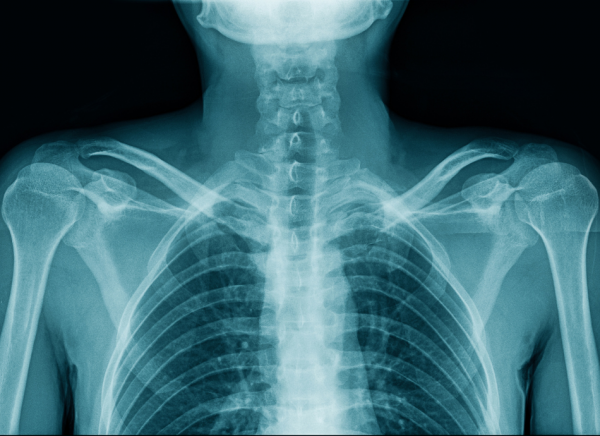

An X-ray uses a small amount of radiation to create images of your bones and internal organs.:

• structures containing air (eg, your lungs) will be black

• muscle, fat, and fluid will appear as shades of grey

• dense structures, eg, bones will block most of the x-ray particles, and will appear white.

Upper body x-ray showing different densities of body parts Image credit: Canva